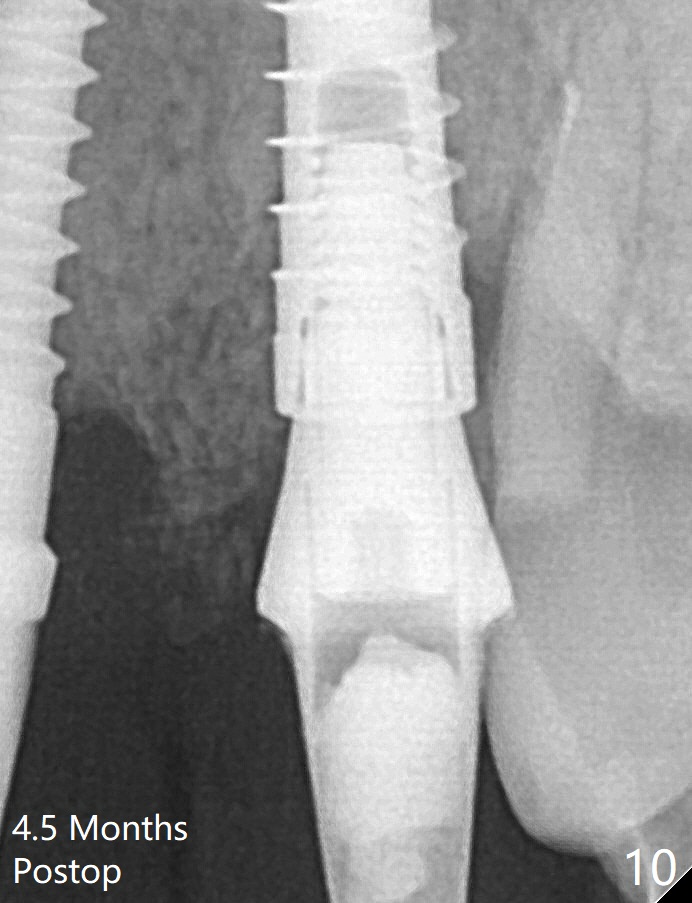

The socket shield at #11 is apparently incomplete, since the apical gutta percha (Fig.2 <) and the apex of the root (Fig.2,3 R) are not removed. The bone is hard when a 1.6 mm drill is being used (Fig.2) as the apical native bone is almost exclusively composed of the cortices. Two of the apical threads of 3.5x13 mm implant are bent, while the implant is placed deeper than the osteotomy (Fig.3,7). After placement of a 4.5x15 degrees A (2mm) angled abutment and Vanilla graft (Fig.7 *), an immediate provisional is fabricated. There is smooth transition from the grafted bone to the native bone 4.5 months postop (Fig.10). Low Magnification, High Magnification of Fig.7,10.